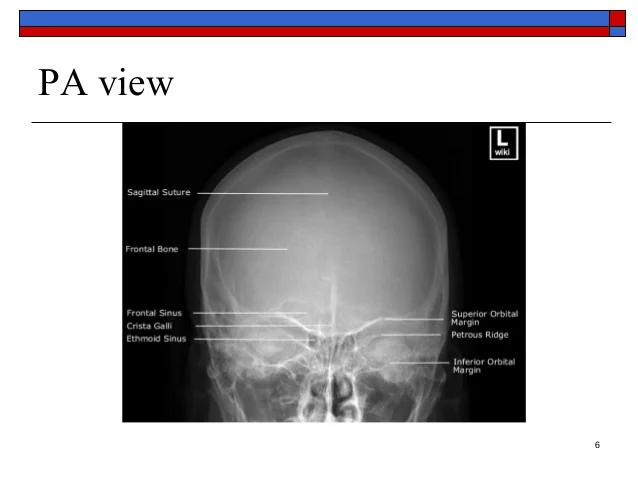

(A)Caldwell 15° 岩部脊在眼眶中的下1/3處

(B)Caldwell 30° 岩部脊切齊下眼眶邊緣

(C)Caldwell 10°由此可知角度愈大,岩部脊愈下面,所以10°絕對比 15°高,這個選項就可以刪掉

(D)PA 0°同(C)的推法

Caldwell 15° 岩部脊是在眼眶中下1/3,而不是眼眶下面1/3

PA的話岩部脊大概會在上眼眶邊緣附近